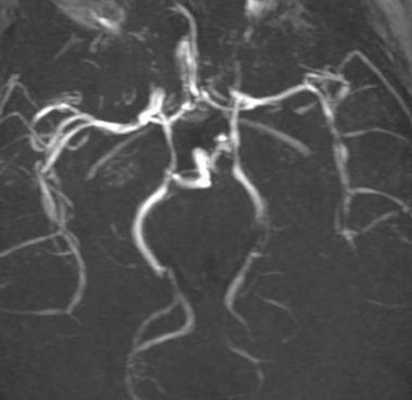

- Церебральная ангиография. Может осуществляться рентгенологически и при помощи МРТ сосудов. По различным данным, выявить сосудистые изменения удаётся у 40-90% больных. На ангиограммах отмечается смазанность сосудистого контура, сужения, участки дилятации, прерывание, окклюзия, наличие множественных коллатералей.

МРА сосудов артериального круга мозга. Выраженное сужение ВСА, СМА и ПМА с обеих сторон.